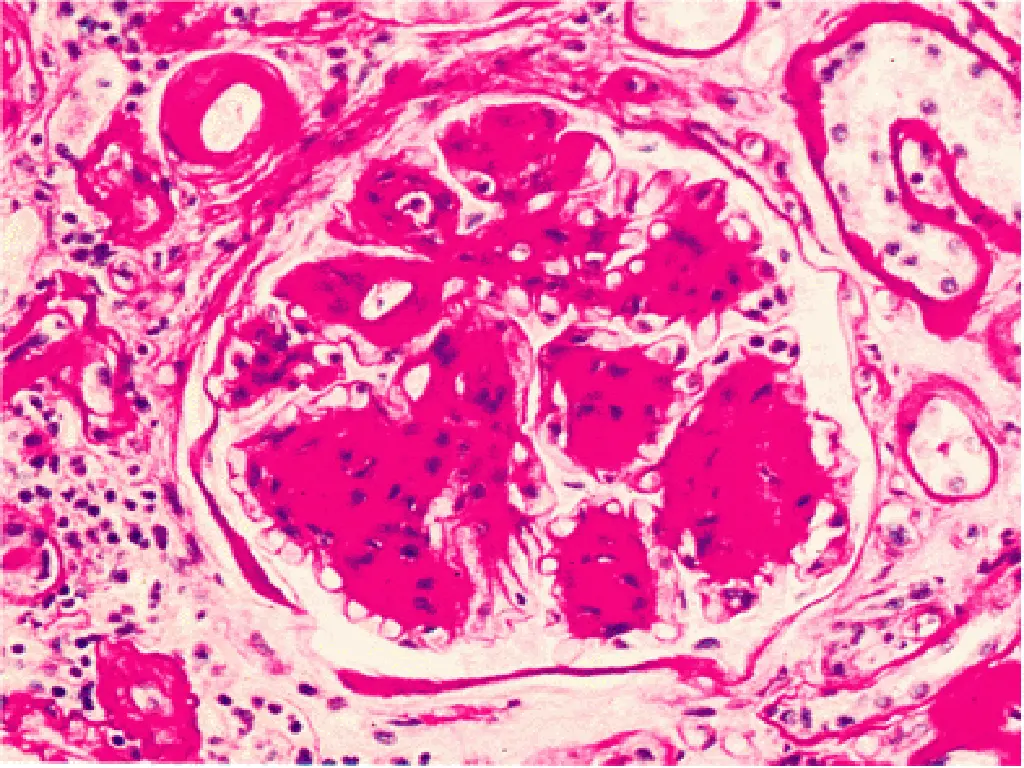

30% to 40% of T1DM ultimately develop renal failure. A somewhat smaller proportion (up to 20%) of patients with T2DM are similarly affected Diabetic nephropathy accounts for one third of all new cases of renal failure. The prevalence of diabetic nephropathy increases with the severity and duration of the hyperglycemia. Kidney disease due to diabetes is the most common reason for renal transplantation in adults. The glomeruli in the diabetic kidney exhibit a unique lesion termed Kimmelstiel-Wilson disease or nodular glomerulosclerosis